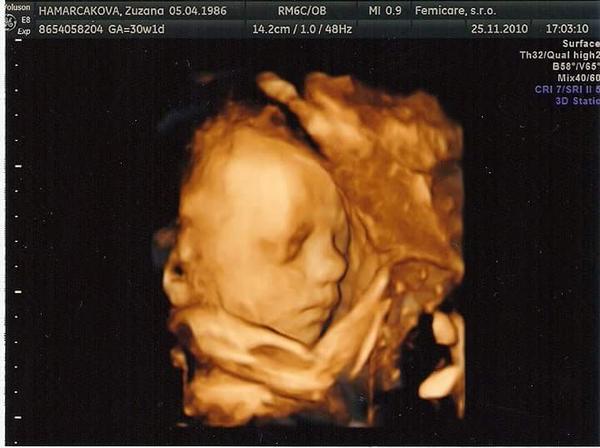

Baby,zvazujem 3/4D utz,kvoli fotkam na pamiatku. Pri petruske mi robila pri kszdom utz,no teraz to nejako sprosto vyslo,mam len z 12tt,v 16tt som mala plny mocovy mechur a nebolo jej vidiet tvaricku,v 20tt zastupoval Dr.,teraz v 24tt bude len krcok.skusat a glukozovy test a potom v 30tt ak to nevyjde,nemam nic ☹ vy ste boli,alebo este len idete,ze? Kolko to stoji?? V gyn five a v kochu? Dobre si pamatam?

@sara22 mojenko no ja idem buduci stvrtok a plati sa v kochu 40e, ja som pri Viktorkovi tiez nebola ale on sa viac ukazal, Alanka mam len jednu foto tvaricky z morfologickeho a aj to rozmazanu lebo cely cas si zakryval tvaricku. Ak chces ist do Kochu tak uz sa objednaj, najlepsie je ist okolo 26-28tt ked este drobec nie je velmi velky a da sa dobre fotit, potom ma uz vraj malo miesta a moze sa stat ze nebude aj tak nic vidiet. Inak sa mas ako? Uz je ti lepsie si zdrava?

@badimeria no to uz v 13tyzdni....prvy organscreening s harmony test...tam Na tom vysetreni